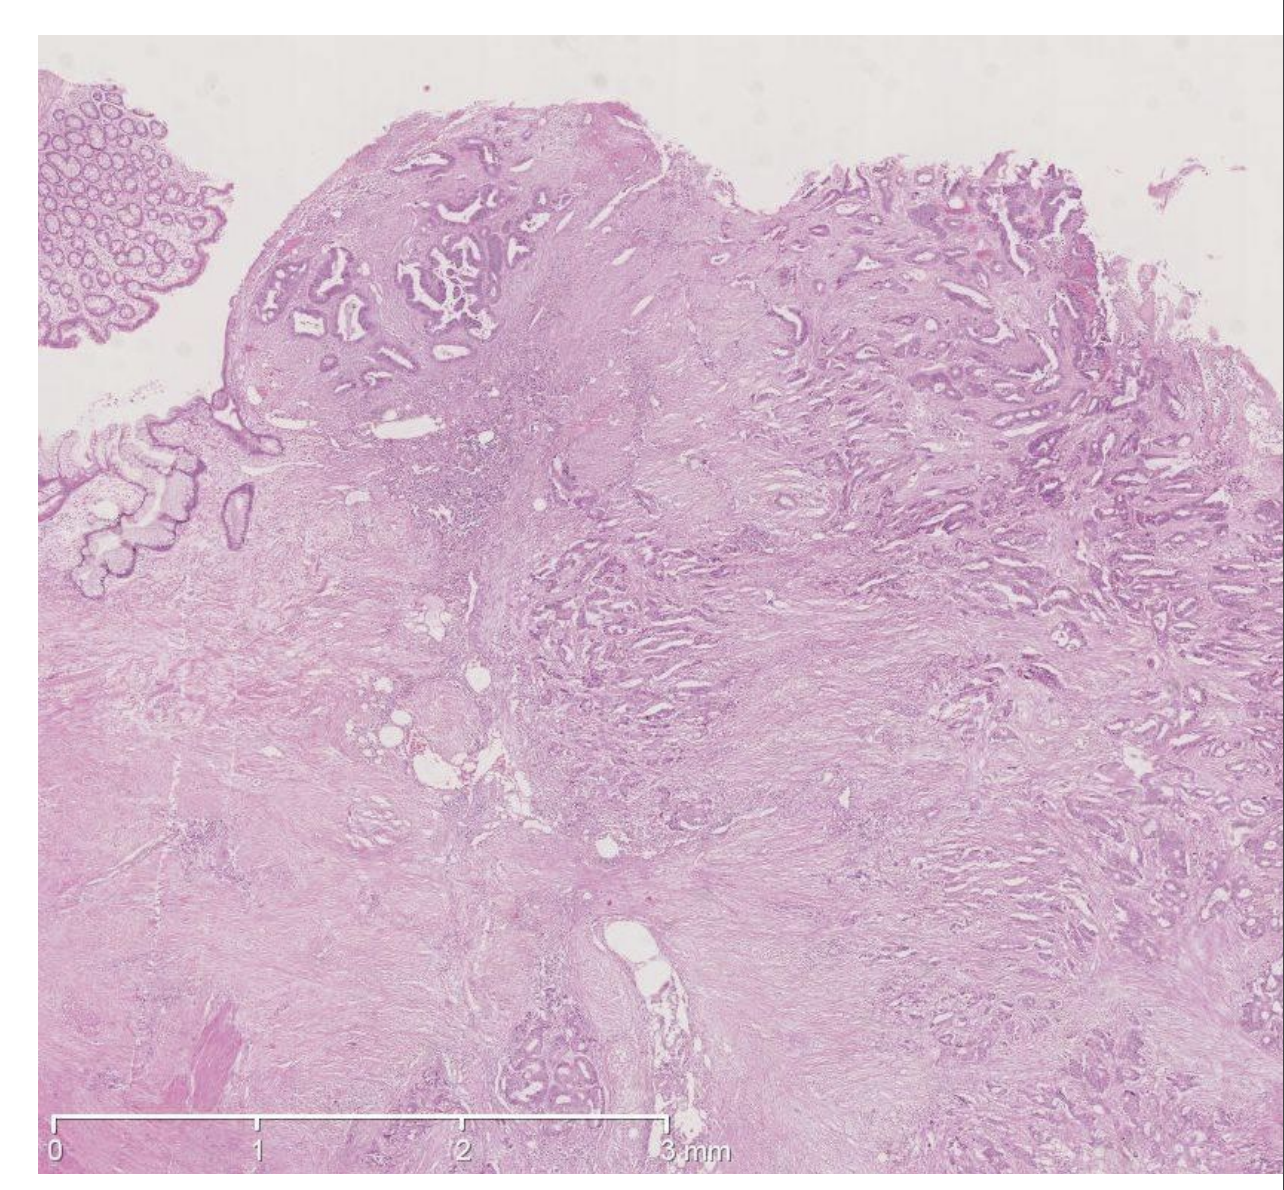

Det mikroskopiske billede fra colon viser

a. Hyperplastisk polyp

b. Adenom med let dysplasi

c. Adenom med svær dysplasi

d. Colitis ulcerosa

e. Adenokarcinom

*e. Adenokarcinom